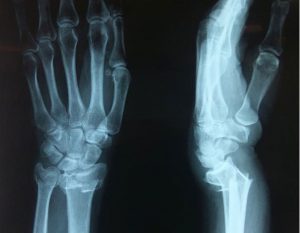

Точно установить вид перелома лучевой кости, возможно после получения результата рентгеновского исследования. Для исключения ошибки обязательным условием является получение снимка в боковой и передней проекции. Такой метод не только подтверждает разлом кости, но и уточняет вид, локализацию травмы, наличие смещения и количество костных отломков. При недостаточной результативности дополнительно назначается магнитно-резонансная томография.